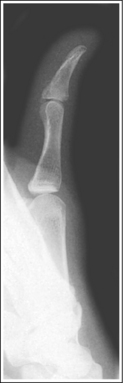

See Figure 4-10 and Box 4-4.

The digit of interest is in a lateral projection. The anterior aspect of the middle and proximal phalanges demonstrates midshaft concavity, and the posterior aspects of the phalanges show slight convexity.

• A lateral finger projection is accomplished by rotating the affected finger 90 degrees from the PA projection (Figure 4-11). Whether the hand is rotated internally or externally to obtain this goal depends on which direction will bring the finger closer to the IR. Typically, when the second and third fingers are imaged, the hand is rotated internally and, when the fourth and fifth fingers are imaged, the hand is rotated externally.

• Distinguishing lateral projection from rotated projection. To understand the difference between a truly lateral digit projection and a lateral projection that is rotated, study a finger skeleton in lateral and PA and AP oblique projections. Note how the midshaft concavity of the middle and proximal phalanges varies as the digit is rotated. In a lateral projection, the anterior aspect of these phalanges is concave, but the posterior aspect demonstrates slight convexity. In PA and AP oblique projections, both sides of the middle and proximal phalangeal midshafts demonstrate concavity, but the side toward which the anterior surface is rotated demonstrates a greater degree of concavity than the side toward which the posterior surface is rotated. The soft tissue width at either side of the phalanx also changes in the lateral and PA and AP oblique projections. More soft tissue is present on the side of the phalanges toward which the anterior surface is rotated (see Image 7).

Concavity is demonstrated on both sides of the middle and proximal phalangeal midshafts, indicating that the finger was not adequately rotated for this image.